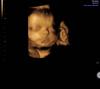

@_sashunya_, личико хорошо было видно на 30 недельке

в 32.1 делала ) все было видно и в 3д и врач все посмотрел)

Я делала 3/4D на 30.3 неделе.